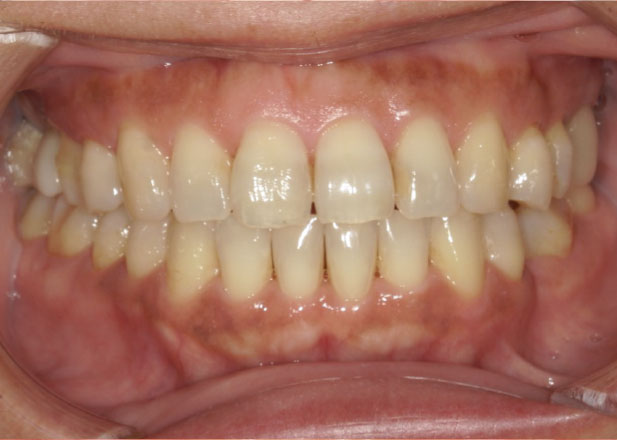

治療前

治療後